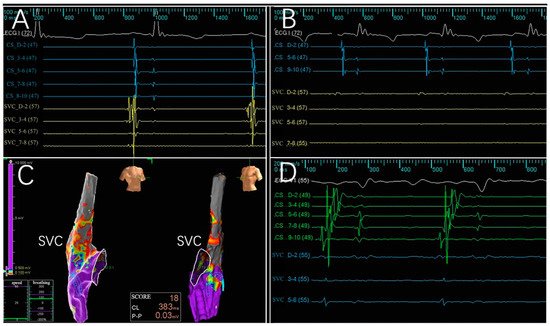

3.2. Electrogram, Voltage Mapping, and Complications